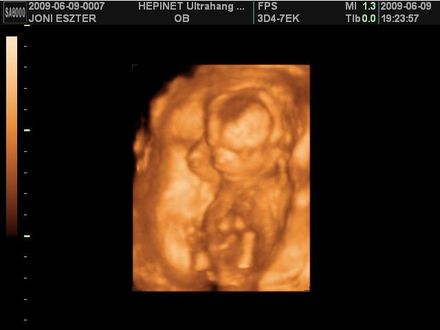

ZSEBIBABA (Milán baba)

Született: 2009. augusztus,

Meghalt: 2009. augusztus

"Pici voltál, még csak 24 hetes... Nagyon vártak már a szüleid, és a rokonaid. Sajnos egy kisebb komplikáció lépett fel, és Anyukádnak meg kellett Téged szülnie. Gyenge voltál még, pedig biztosan küzdöttél, hogy ezen a csodás Világon éljél Te is! Sajnos hiába, az Angyalok magukhoz szólítottak, és most már ők vigyáznak Rád, Drága kis Zsebibaba!"

ZSEBIBABA